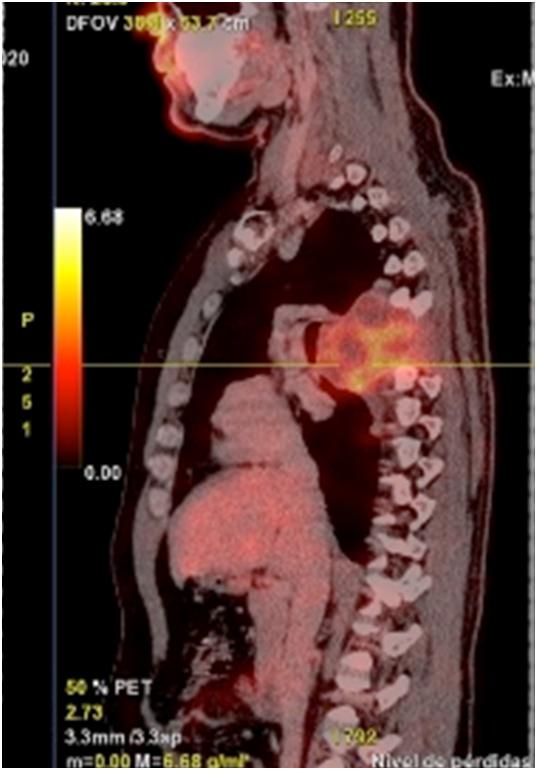

Como conclusión, este estudio confirma la gran efectividad diagnóstica de la PET para las indicaciones oncológicas y demuestra que sus resultados tienen una gran influencia en el manejo clínico y terapéutico de estos pacientes. El Servicio Nacional de Salud ha incorporado esta tecnología como una más de sus prestaciones.